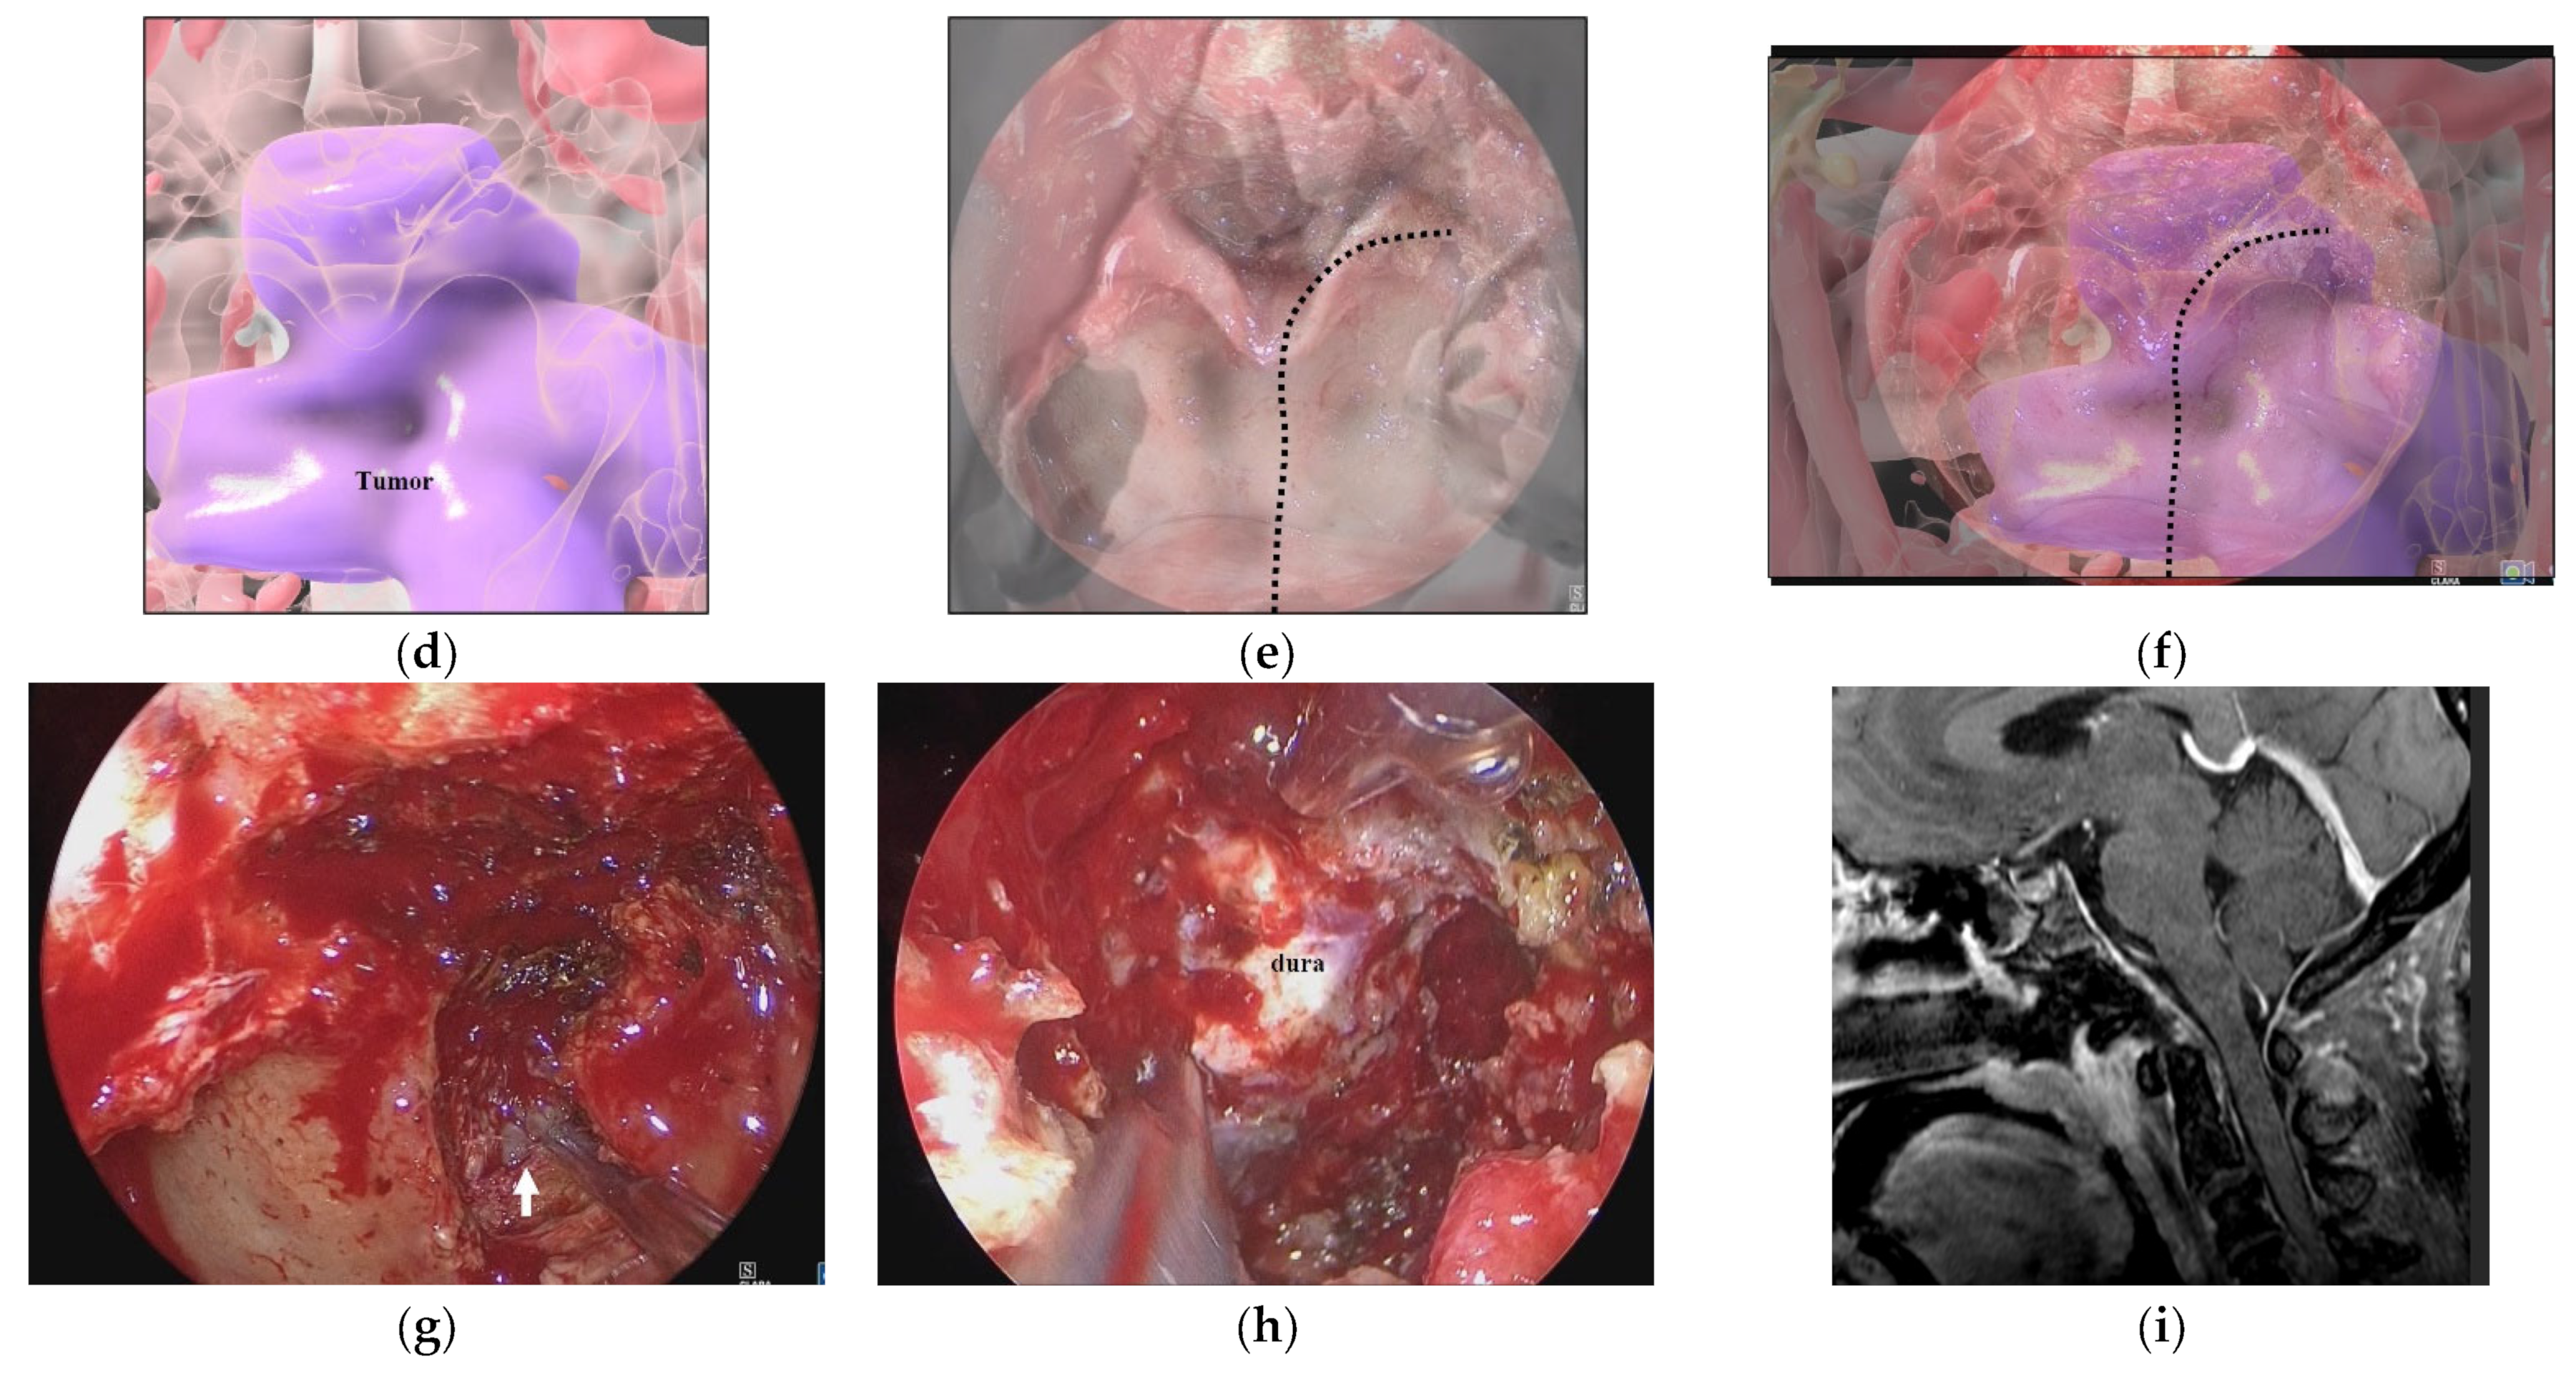

3.1. Illustrative Case 1 (Case 4)